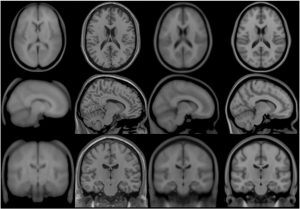

Transverse, sagittal and coronal views of four generations (all T1-weighted images) of MNI space template from left to right. Note that MNI52 has greater z-axis coverage than MNI305 and that the 40th-generation non-linear MNI152 combines the detail apparent in the single subject Colin27 template with the group representativeness of MNI305 or MNI152.

MNI305 T1 atlas

In the early 1990s, Evans and colleagues introduced the concept of a statistical MRI atlas for brain mapping in order to overcome the idiosyncrasies of using a single subject brain as a template (Evans et al., 1992a,b, 1993). The MNI305 atlas was constructed in two steps.

First, anatomical landmarks were manually identified in T1-weighted MRI scans from young healthy subjects. These landmarks were chosen from the Talairach and Tournoux atlas and thus the final average and space approximated Talairach space. Landmarks from each subject were fitted together via least-squares linear regression that matched the resulting AC-PC line to the original Talairach and Tournoux atlas. This yielded a first-pass average T1-weighted MRI volume.

Second, each native MRI volume was automatically mapped to the manually-derived average MRI to reduce the impact of order effects, manual errors and to create a sharper average. The mapping was not performed according to Talairach’s piecewise linear model but used a whole-brain linear (9-parameter) image similarity residual (Collins et al., 1994). The resultant template is thus an approximation of the original Talairach space and the Z-coordinate is approximately +3.5 mm relative to the Talairach coordinate. This process resulted in the original MNI305 atlas that has subsequently defined the MNI space. Note that, under constraints of linear alignment, residual non-linear anatomical variability across subjects gives rise to a “virtual convolution” (Evans et al., 1993) that somewhat enlarges the template compared with most individual brains.